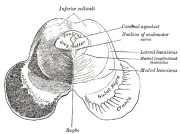

| 2021年7月26日 (一) 18:31 | Gray711.png (文件) |  |

27 KB | 77921020 | Uploaded with SimpleBatchUpload | 1 |